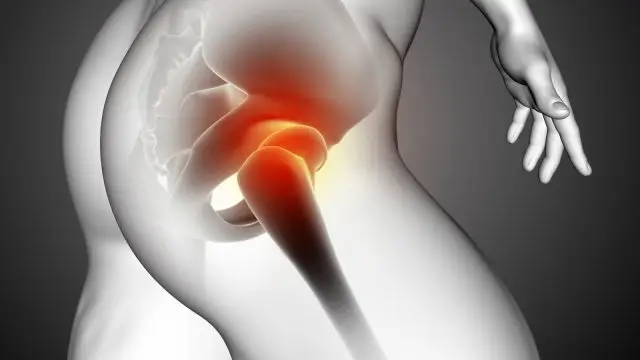

Kalça Anatomisi ve Minimal İnvaziv Kalça Protezi

Kalça eklemi, vücudun en büyük ve en fazla yük taşıyan eklemlerinden biridir. Femur başı (uyluk kemiği topu) ile asetabulum (pelvis soketi) arasında yer alan bu eklem, top-soket yapısı sayesinde hem sağlamlık hem de geniş hareket kabiliyeti sağlar. Eklem yüzeyini kaplayan eklem kıkırdağı, kemiklerin birbirine sürtünmeden hareket etmesini sağlar. Ayrıca, kalça

Kalça Ağrısı Nedir?

Kalça ağrısı, günlük yaşamı doğrudan etkileyen ve pek çok farklı sebeple ortaya çıkabilen yaygın bir ortopedik sorundur. Kalça eklemi, vücudun ağırlığını taşıyan en önemli eklemlerden biridir ve yürüme, oturma, koşma veya eğilme gibi hareketlerde aktif rol oynar. Bu nedenle eklem, kas, sinir veya kemik yapısında oluşan herhangi bir problem, kalça